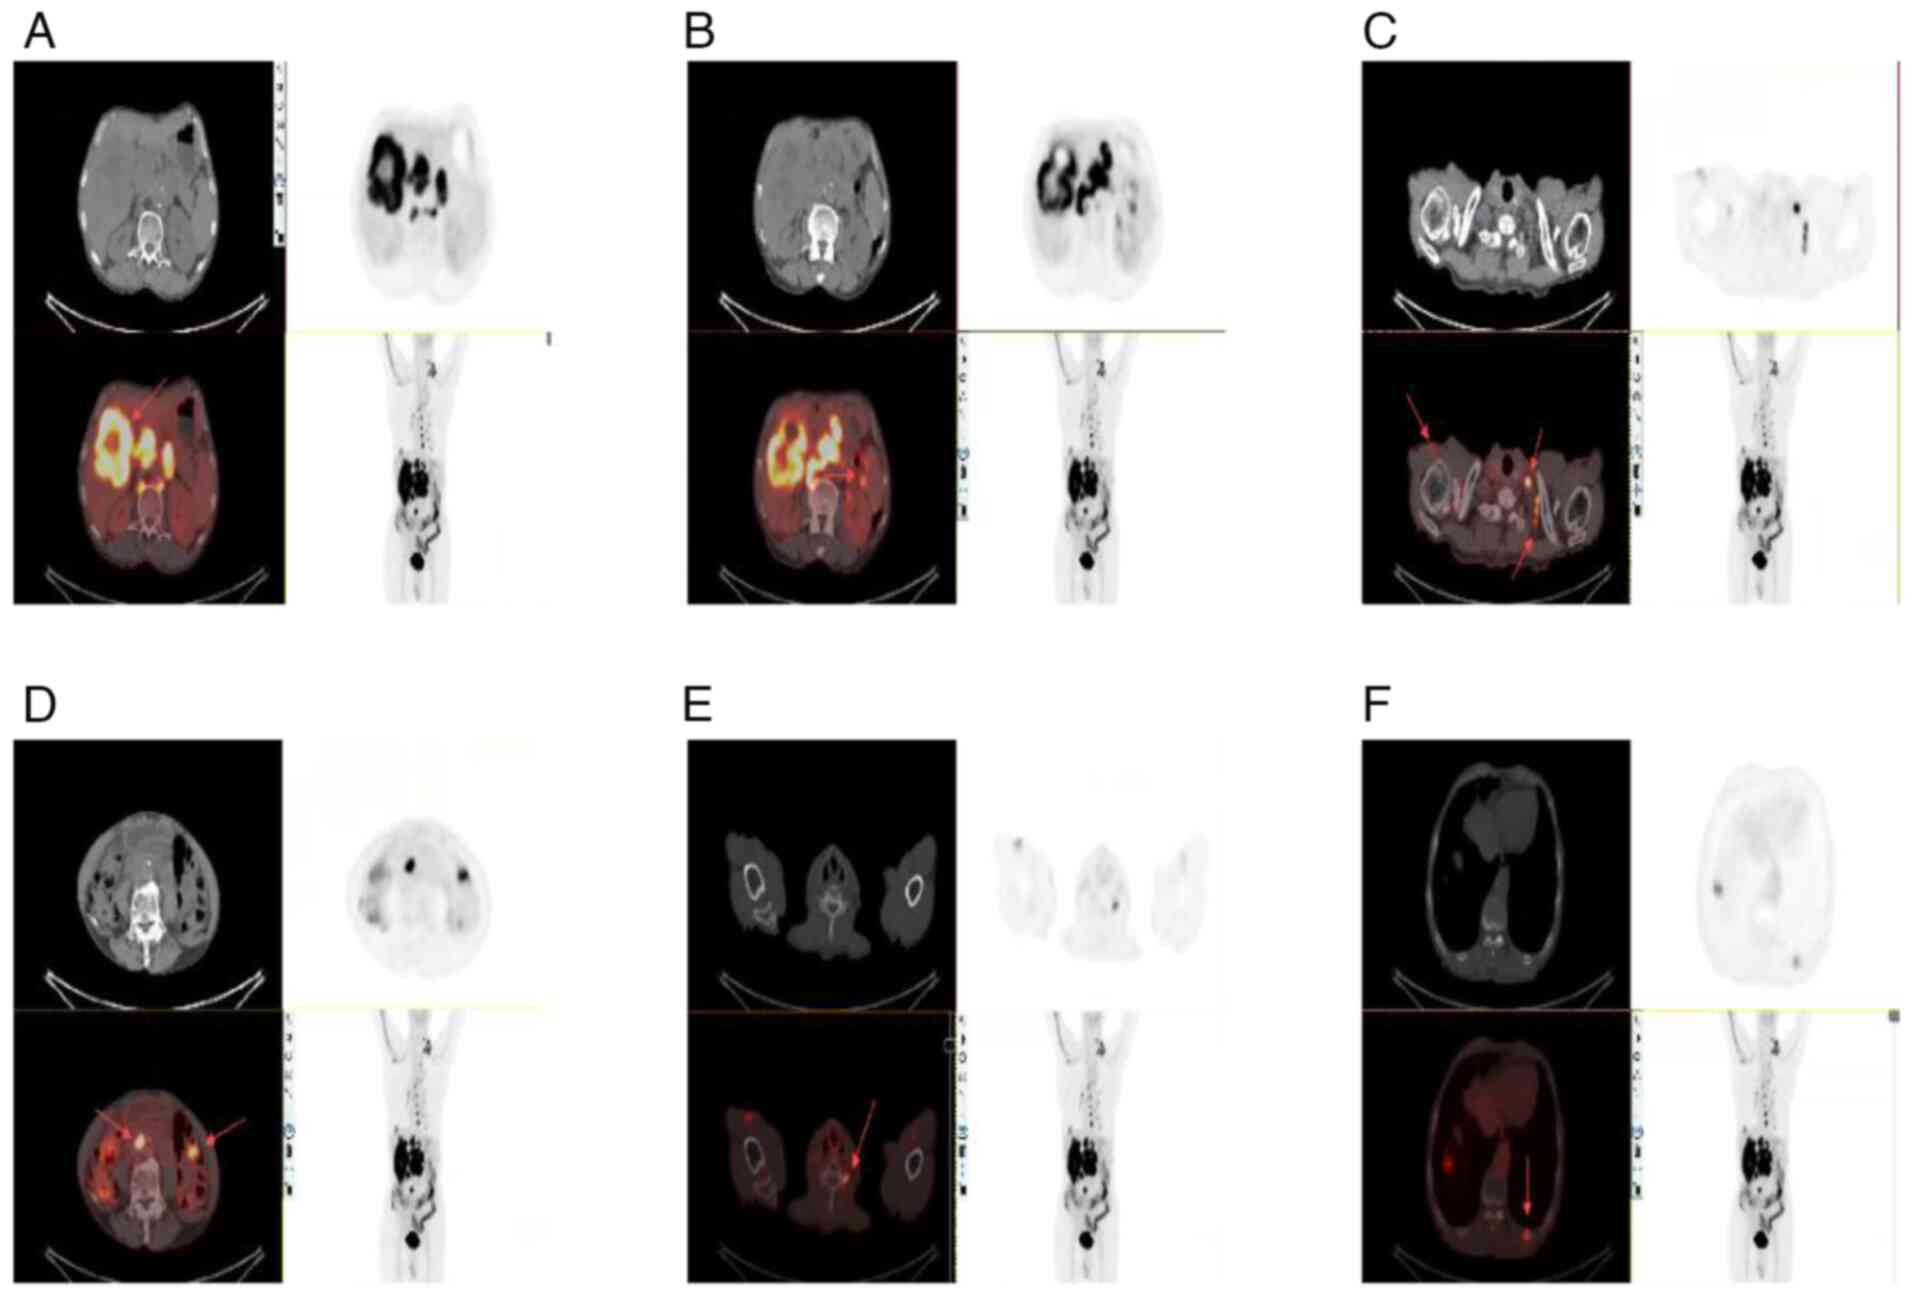

Given the rarity of hepatic SCC, a positron emission tomography (PET)/CT scan was performed to exclude the possibility of metastases from other primary sites. The PET/CT findings were as follows: An irregular mass was observed in the right lobe of the liver (Fig. 3A). Multiple low-density nodules were identified within the liver, as well as multiple enlarged lymph nodes in the hepatic hilum, posterior to both diaphragmatic crura, around the abdominal aorta in the retroperitoneum, and at the root of the mesentery (Fig. 3B). Additional enlarged lymph nodes were noted in the upper abdominal peritoneal area, posterior mediastinum, around the esophagus, the right axillary area (Fig. 3C) and the left clavicular area (Fig. 3D). Bone destruction was observed in the left transverse process of the sixth cervical vertebra (Fig. 3E), and in the left 10th and 11th posterior ribs (Fig. 3F), suggestive of metastases.

Figure 3.

Positron emission tomography/computed tomography images demonstrating disease progression. (A) Irregular mass in the right lobe of the liver suggesting a primary hepatic lesion (SUVmax, 14.0) (B) Bilateral enlarged lymph nodes posterior to the diaphragmatic crura, around the abdominal aorta in the retroperitoneum and at the mesenteric root (SUVmax, 14.9). (C) Multiple enlarged lymph nodes in the left clavicular region and right axilla (SUVmax, 4.5–12.4). (D) Lymph node metastases in the upper abdominal peritoneal region and around the thoracic aorta (SUVmax, 4.21–15.36). (E) Bone metastasis involving the left transverse process of the sixth cervical vertebra. (F) Bone destruction of the left 10th and 11th posterior ribs indicative of bone metastasis (SUVmax, 6.1). SUVmax, maximum standardized uptake value.

The increased glucose metabolism observed in these regions suggested a primary malignant hepatic lesion, possibly intrahepatic cholangiocarcinoma, with intrahepatic metastasis, multiple lymph node metastases and bone metastases. No other primary tumors were detected. Based on the pathology and imaging findings, a final diagnosis of PSCCL was made.